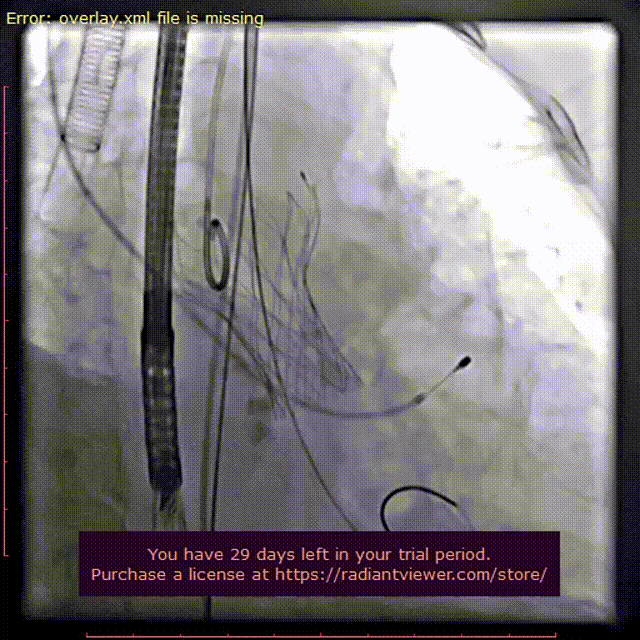

主动脉根部造影提示主动脉瓣轻度反流,根部钙化较重,180次起搏下予以22mm球囊充分预扩,球囊出现明显腰征,无造影剂渗漏,冠脉显影正常。

主动脉根部造影

球囊预扩